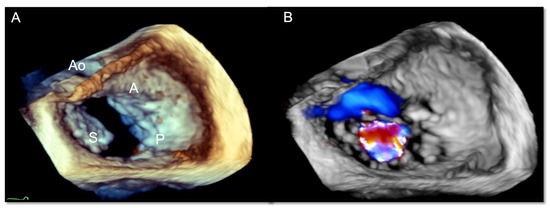

3.1. Two-Dimensional and Three-Dimensional Transesophageal Echocardiography

- Ancona, F.; Stella, S.; Taramasso, M.; Marini, C.; Latib, A.; Denti, P.; Grigioni, F.; Enriquez-Sarano, M.; Alfieri, O.; Colombo, A.; et al. Multimodality imaging of the tricuspid valve with implication for percutaneous repair approaches. Heart 2017, 103, 1073–1081. [Google Scholar] [CrossRef] [PubMed]

- Agricola, E.; Ancona, F.; Stella, S.; Rosa, I.; Marini, C.; Spartera, M.; Denti, P.; Margonato, A.; Hahn, R.T.; Alfieri, O.; et al. Use of Echocardiography for Guiding Percutaneous Tricuspid Valve Procedures. JACC Cardiovasc. Imaging 2017, 10, 1194–1198. [Google Scholar] [CrossRef]